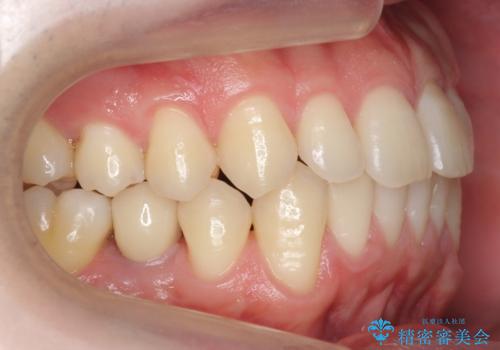

- 前歯の並びをきにして来院。

歯を抜かずに、やすりがけすることでスペースを獲得し、前歯をしっかり下げました。

また、インビザラインに先駆けて、右下はワイヤーによる部分矯正を行い、犬歯をしっかり後ろに下げました。

下げる時に、矯正用ミニスクリューを使用しています。